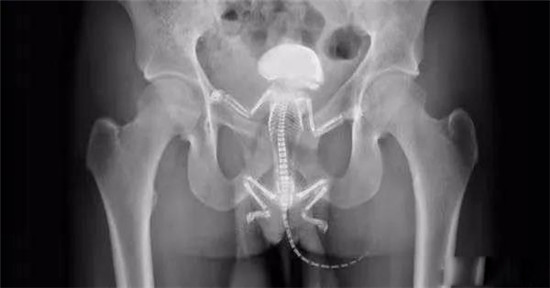

透视下从肛门里夹取直肠里的东西

一只松鼠在直肠里。

松鼠把他的直肠抓破了,最后松鼠死在他的直肠里,医生只好给他开刀取出来了。

在我国,最常见的,出现在直肠里的动物是黄鳝或者泥鳅。出事情最多的是黄鳝。

这条黄鳝还是雌性的黄鳝,你知道我怎么看出来的吗?

医生给他检查的时候,发现已经有腹膜炎症状,怀疑肠梗阻,拍了个片子,就是上面那个片子:一条大黄鳝在肚子里。

考虑到他已经有腹膜炎的症状,说明肠子已经有个地方破了。只能动手术了。

把肚子打开后,发现大肠破了个洞,黄鳝的头,就在那个洞里。他肚子里都是大便。他的肠子水肿很厉害。黄鳝堵住了大肠,肠梗阻,导致大肠坏死穿孔了。